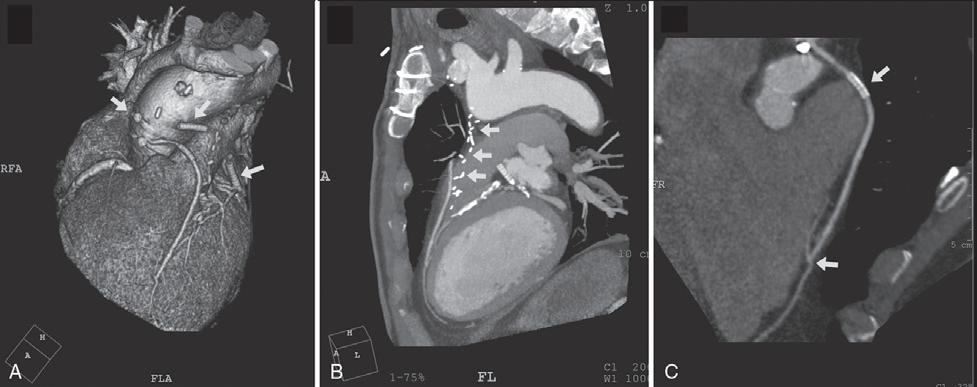

E-FIGURE 1-1 Devices that are increasingly available to provide assistance during high-risk percutaneous coronary intervention (PCI) include percutaneous extracorporeal circulatory support devices such as (A, B) the TandemHeart and (C) the Impella device. (A) The TandemHeart removes oxygenated blood from the left atrium and returns this blood into the peripheral arterial circulation; with the (B) aid of a centrifugal pump. C, The Impella left ventricular assist device is a miniaturized rotary blood pump that is placed retrograde across the aortic valve, and it aspirates (inlet area) up to 2.5 L/min of blood from the left ventricular cavity and subsequently expels this blood (outlet area) into the ascending aorta. (From Valgimigli M, Steendijk P, Serruys PW, et al: Use of Impella Recover LP 2.5 left ventricular assist device during high-risk percutaneous coronary interventions; clinical, haemodynamic and biochemical findings. EuroIntervention 2[1]:91-100, 2006; and Vranckx P, Meliga E, De Jaegere PP, et al: The TandemHeart, percutaneous transseptal left ventricular assist device: a safeguard in high-risk percutaneous coronary interventions. The six-year Rotterdam experience. EuroIntervention 4:331, 2008.)